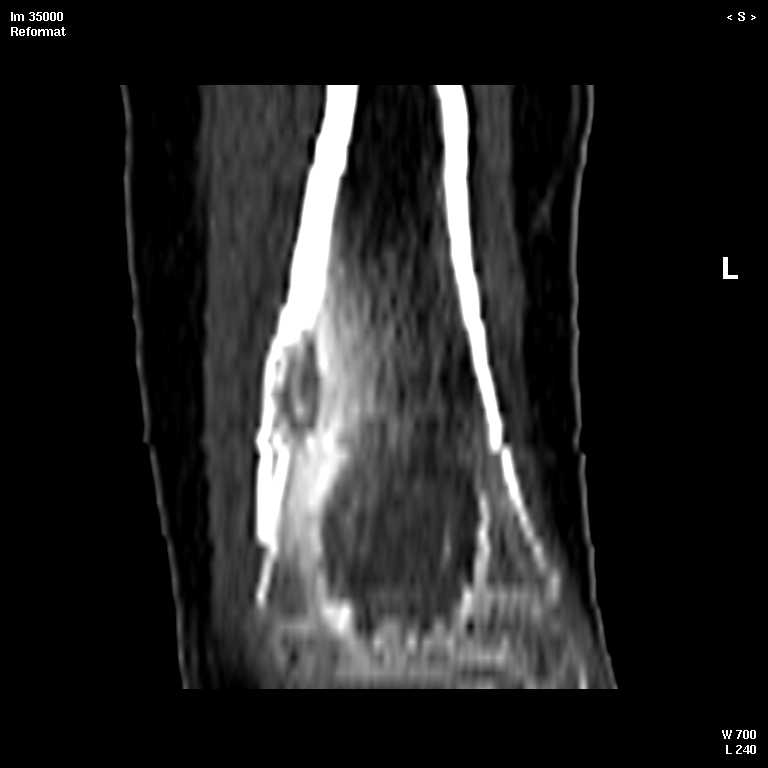

В обсуждении темы возникла необходимость дополнительных данных.

КТ изображения передаю на мой взгляд самые демонстративные. Их любезно записал коллега,

проводивший исследование в другом городе.